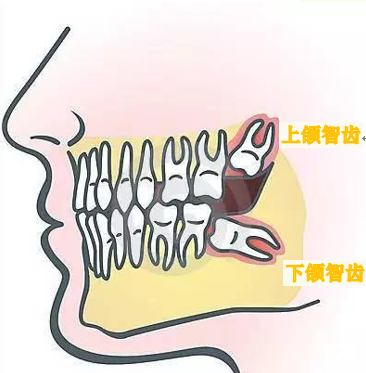

什么是智齿?

所谓的智齿,也就是第三磨牙,一般于16~25岁萌出,这时候人的心理生理发育均趋于成熟,所以这时候萌出的这颗牙齿被看作是智慧的象征,智齿本身其实与智力并无任何关系。

随着人类的饮食的精细,颌骨逐渐变小,而牙齿大小没有明显变化,这就导致了牙量大于骨量,所以智齿因为生长空间的受限往往萌出受阻或异位生长,甚至还会挤压前面的第二磨牙,这就会造成智齿区牙龈肿痛、邻牙损伤,颞颌关节病,并成为牙源性囊肿及肿瘤、面部肿胀、面部间隙感染、张口受限等不适症状,严重的可能会引起发烧等全身症状。